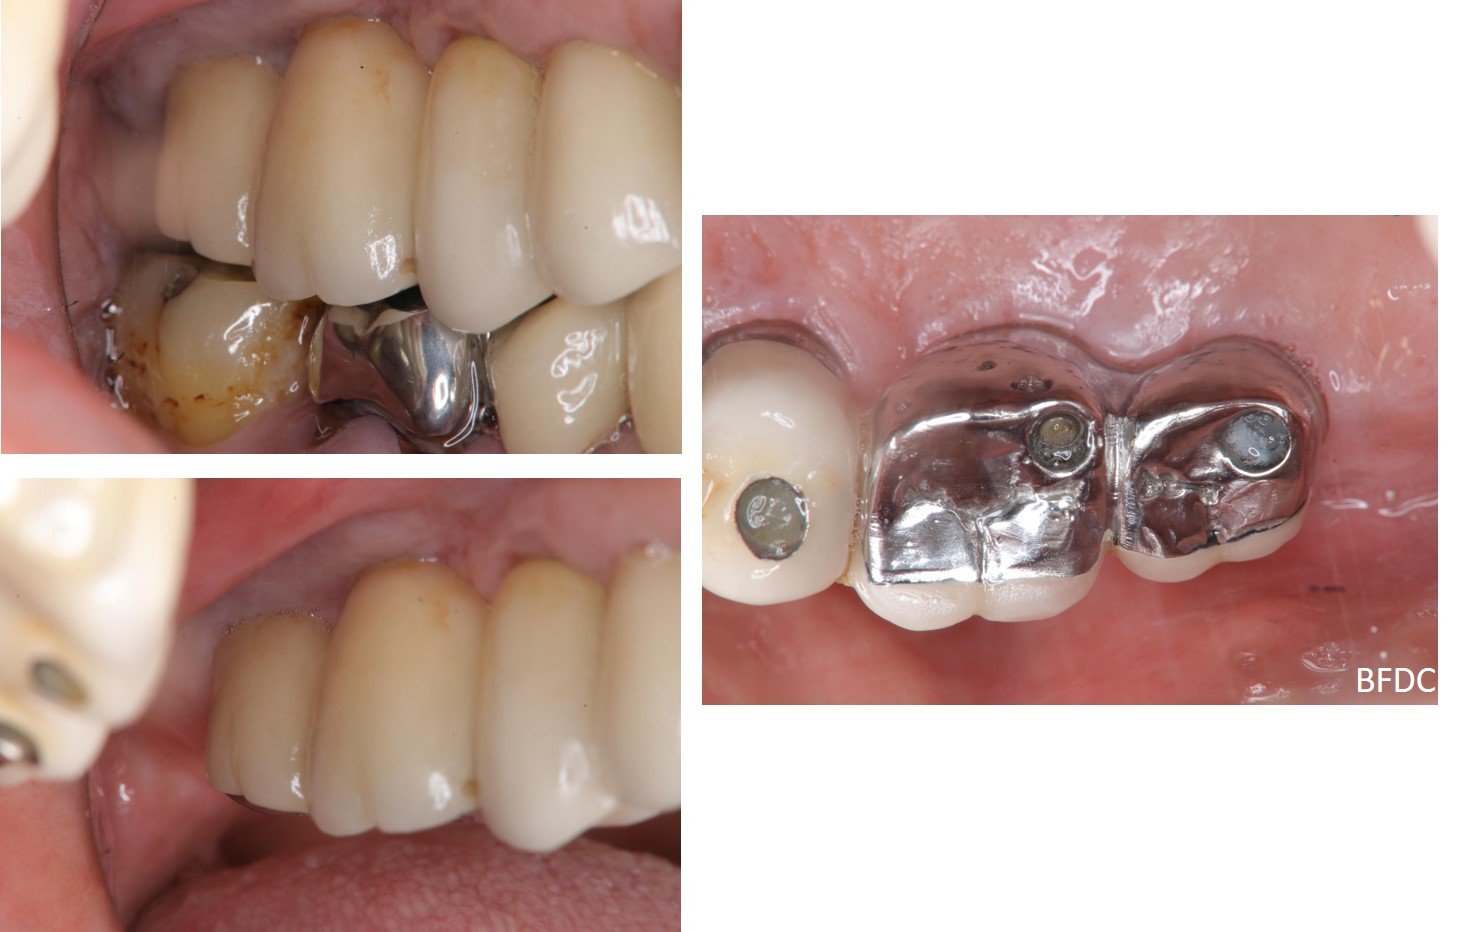

螺絲固定式臨時假牙

錐狀植體支柱

螺絲固定式假牙

金屬燒付螺絲固定式瓷牙